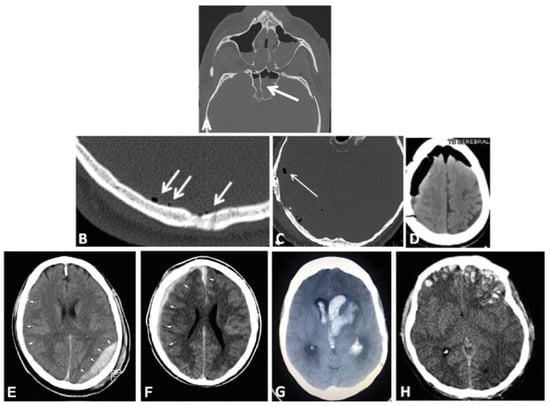

Associated Intracranial Features

A list of clinically relevant intracranial features that may be associated with skull base and/or cranial vault fractures is proposed in addition to the fracture classification system to support the diagnosis and decision process (Table 2). These features include the presence of intracranial air (0 = none, 1 = single, or multiple air bubbles [up to 3 mm diameter], 2 = pneumocephalus [larger air pockets > 3mm]) (Figure 4B–D), intracranial mass lesion (epidural, subdural, subarachnoid, intraventricular, and/or intraparenchymal hematoma, brain contusions, foreign bodies) (Figure 4E–H), as well as radiological or clinical evidence of dural rupture, with following cerebrospinal fluid (CSF) leak.

Figure 4. Examples of associated diagnostic features with skull base and cranial vault fractures. (A) Partial opacification in the sphenoid sinus with air–fluid level in computed tomographic imaging (representing possible the presence of blood or fluid). (B–D) Presence of intracranial air: single or multiple air-bubbles in the subdural spaces (arrows in B) or in the subarachnoid space (arrow in C); (D) pneumocephalus. (E–H) Intracranial mass lesions: (E) epidural hematoma in the left occipital region (arrowheads) with small mixed (epidural and subdural) hematoma in the right temporal region (arrows), (F) subdural hematoma of the right hemisphere (arrows) with extension along the falx (arrowhead), (G) intraventricular haematoma, (H) brain contusions.